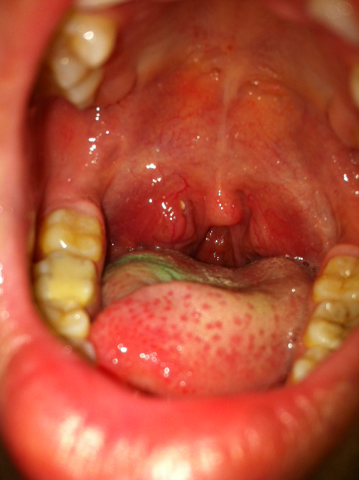

问:嗓子扁桃体发炎貌似起泡怎么办

主要症状:         高热,嗓子痛,食欲差,口腔及咽喉出现灰白疱疹.